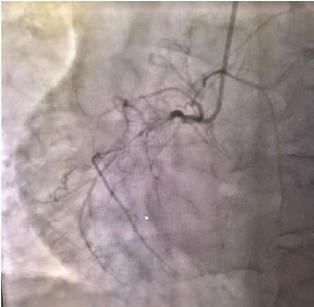

Coronary anatomy revealed a normal left main and an occlusion in the ostial left anterior descending (LAD) at 95%, proximal LAD 70%, mid-LAD 90%, mid left circumflex (LCx) 85%, obtuse marginal (OM)1 70%, OM2 40%, 1st left posterolateral artery 70%, ostial left posterior descending artery 90%, and a right coronary artery (RCA) 100% chronic total occlusion (CTO) (Figures 2-4).